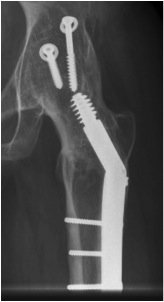

Extra-articular Intra-articular Combined intra-articular + anterior plate

Hip Fusion Cobra Plate Hip Fusion AP Hip Fusion 1Hip fusion 2

Fixation

- 150° DHS / 6.5 mm cannulated screws

- through joint into thick supra-acetabular area of ilium

- supplement with additional screws as necessary

Anterior plate onto lateral aspect of iliac crest